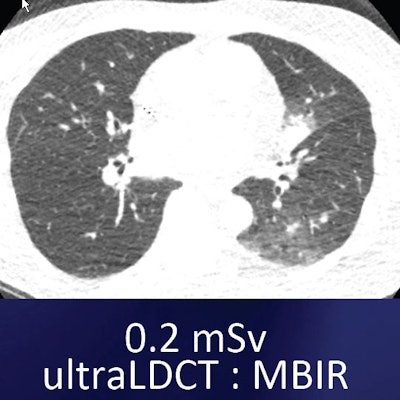

Small nodule in left lung base can be seen both in the standard low-dose filtered back projection (FBP) technique (above) and the ultralow-dose MBIR technique (below). However, the images look inherently different, which may take some getting used to. All images courtesy of Dr. Ella Kazerooni.

For example, one commercially available MBIR protocol (Veo, GE Healthcare) has shown an impressive ability to reduce noise and improve contrast and spatial resolution, she said. The technique, cleared by the U.S. Food and Drug Administration (FDA) in 2011, uses advanced modeling of system statistics and optics to increase spatial and contrast resolution while permitting vastly lower radiation doses -- as low as 0.2 mSv -- in the lungs.